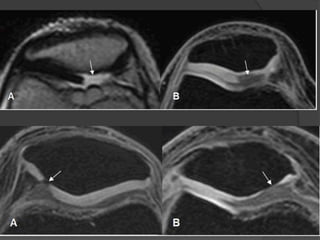

 1=Presencia de señal intrameniscal que contacta con la

superfcie articular

 Hiperseñal intrameniscal= degeneración mucinosa

 Identificar lesión en 2 proyecciones

 2=Morfología meniscal anómala

 A menudo es hallazgo sutil de rotura meniscal con 2

excepciones (menisco discoide y la ondulación o buckling)

Buckling

 Ondulación meniscal se

considera una variante

posicional caracterizada

por un pliegue unico

simétrico a lo largo del

borde libre del menisco

 Se presenta en flexión,

valgo y rotación externa